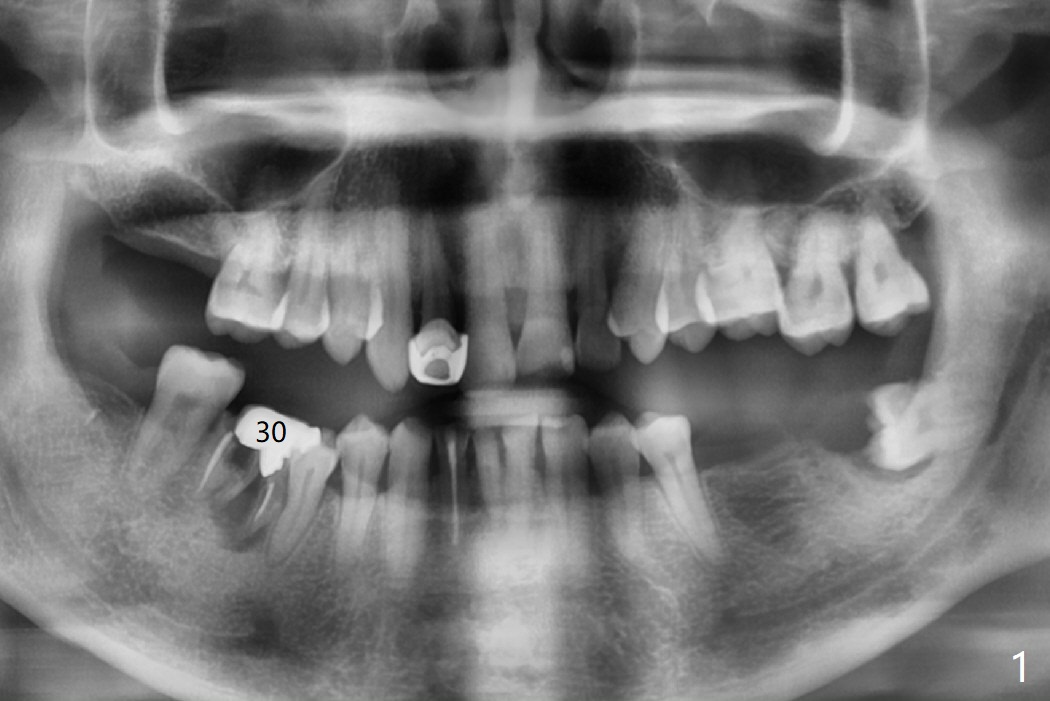

A 61-year-old man presented to clinic for new patient examination last year (Fig.1). He was not interested in extraction and implant at #30 because of finance. This year he requested treatment since he cannot chew well (Fig.2). After exam, extraction and implant at #30 appear not to be a priority, since there is anterior deep bite (Fig.3) with posterior occlusal collapse (Fig.4) as well as #29 malposition.